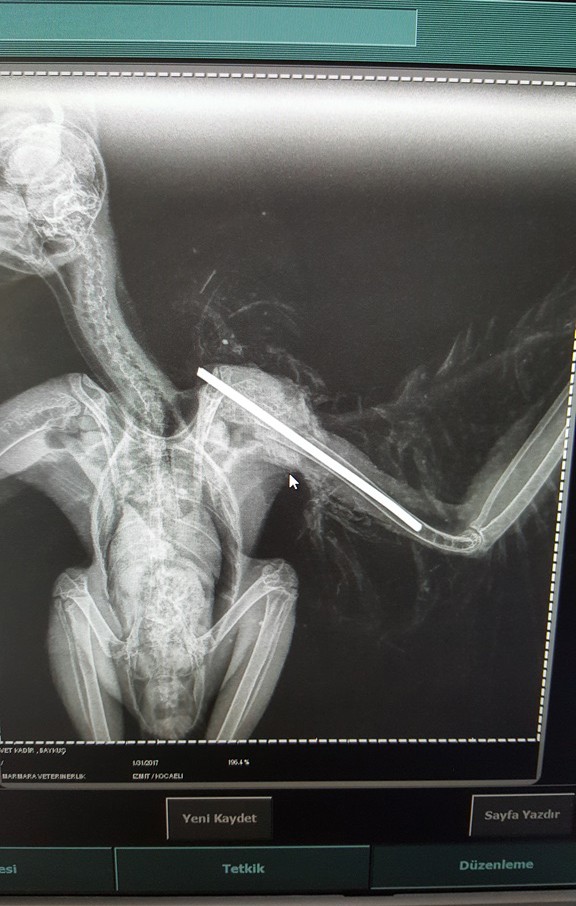

Kocaeli Büyükşehir Belediyesi'nin Doğal Yaşam Parkı'na getirilen peçeli baykuşun kırılan sol kanadına platin takıldı. Peçeli baykuş, uçmayı başarabilirse yeniden doğaya bırakılacak.

Yarıla halde bulunan baykuş Kocaeli Büyükşehir Belediyesi Doğal Yaşam Parkı görevlilerine teslim edildi. Nedeni belirlenemeyen bir kaza sonucu kanadı kırılan peçeli baykuş, yapılan muayenesinin ardından ameliyata alındı. Doğal Yaşam Parkı sorumlusu Veteriner Hekim Abdülkadir Köybaşı ve veterinerler baykuşun kırılan sol kanadına ameliyatla platin yerleştirdi. Baykuş ameliyat ardından bakıma alındı. Veteriner hekim Abdülkadir Köybaşı, 2 hafta önce parka getirilen baykuşun kanadının parçalanmış olduğunu belirterek, şöyle dedi:

"İlk olarak acil müdahalesini yaptık, sonra kanadının durumunu düzeltmek için bir operasyon geçirmesini uygun gördük. Veteriner hekim arkadaşlarımızla operasyon ile baykuşun kanadına platin yerleştirdik. Şu ana kadar baykuşumuzun durumu iyi, ameliyatın komplikasyonlarını atlattı. Kanadının kırığının iyileşmesinden sonra platinini çıkarıp kanadının toparlayıp toparlamadığına bakacağız. Çünkü kaslarında da çok hasar vardı, kanadını da eskisi gibi kullanamama ihtimalini de göz önünde bulunduruyoruz. Onun için eğer uçmayı başarabilirse doğaya geri salacağız. Burada hayvanımızın beslemesini sağlıyoruz. Gece karanlıkta yiyor. Verdiğimiz besinleri bir süre ılık suda bekletip, sanki bir hayvanı kendi tutmuş da yiyormuş algısı oluşturarak beslemesini yapıyoruz. Uçmayı başaramazsa biz burada onun ömrünün geri kalan kısmını en rahat şekilde geçirebilmesi için uygun koşulları oluşturacağız. Doğal Yaşam Parkı olarak hedefimiz bu."